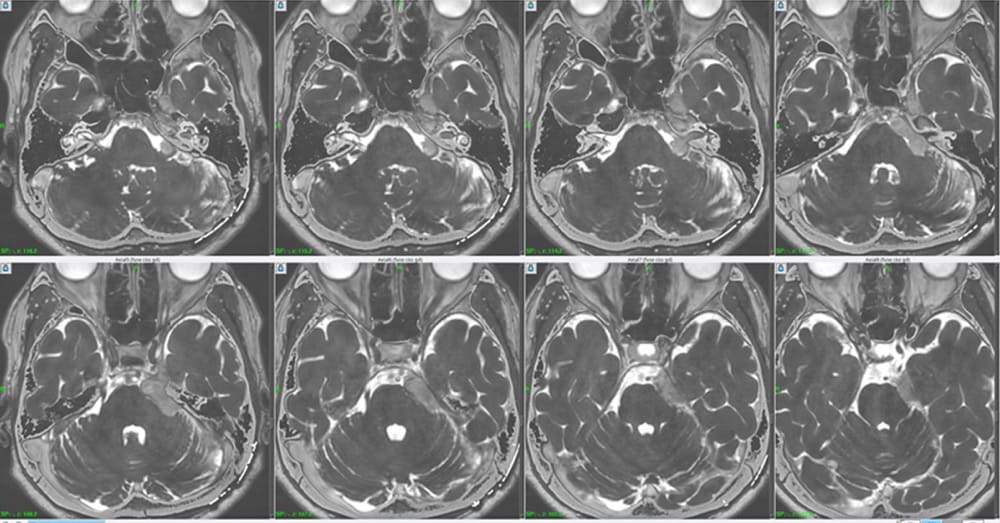

Gd造影CISS/FIESTA axial view

そして上図のごとく、本症例に対してGd enhanced CISS/FIESTA axial viewを撮像し、海綿静脈洞システムおよび腫瘍自体がtransparentとなるべく、微小解剖学的識別目的で施行した。そして、腫瘍はやはりテント(主に上錐体静脈洞内側壁)発生であることが分かり、テント上錐体静脈洞内側壁より後頭蓋窩へ成長進展したものがpetroclival junctionに達し、その後に後方よりメッケル腔内に進展していることが判明した。よって、メッケル腔底において、前方下方に髄液陰影を見ることができた。一方で、テント内側壁より内側、つまり上錐体静脈洞内へ成長進展を認めたが、幸い海綿静脈洞内への進展には至らず、よってDorello’s canal および Basilar venous plexusへの腫瘍進展も存在しなかった。本腫瘍では往々にして、錐体静脈洞外側壁より中頭蓋窩側へ成長進展していくタイプもあるが、本症例ではそれは認めなかった。

左から:

動眼神経

外転神経

三叉神経

聴神経・顔面神経

その後、実際に治療計画を立てる際に、腫瘍および周囲正常脳神経との微小解剖を把握する必要あり、治療計画コンピュータ内にて3次元的に正確に把握すべく努力した。結果、上図のように、腫瘍と動眼・外転・三叉・聴・顔面神経をそれぞれ描出に成功した。